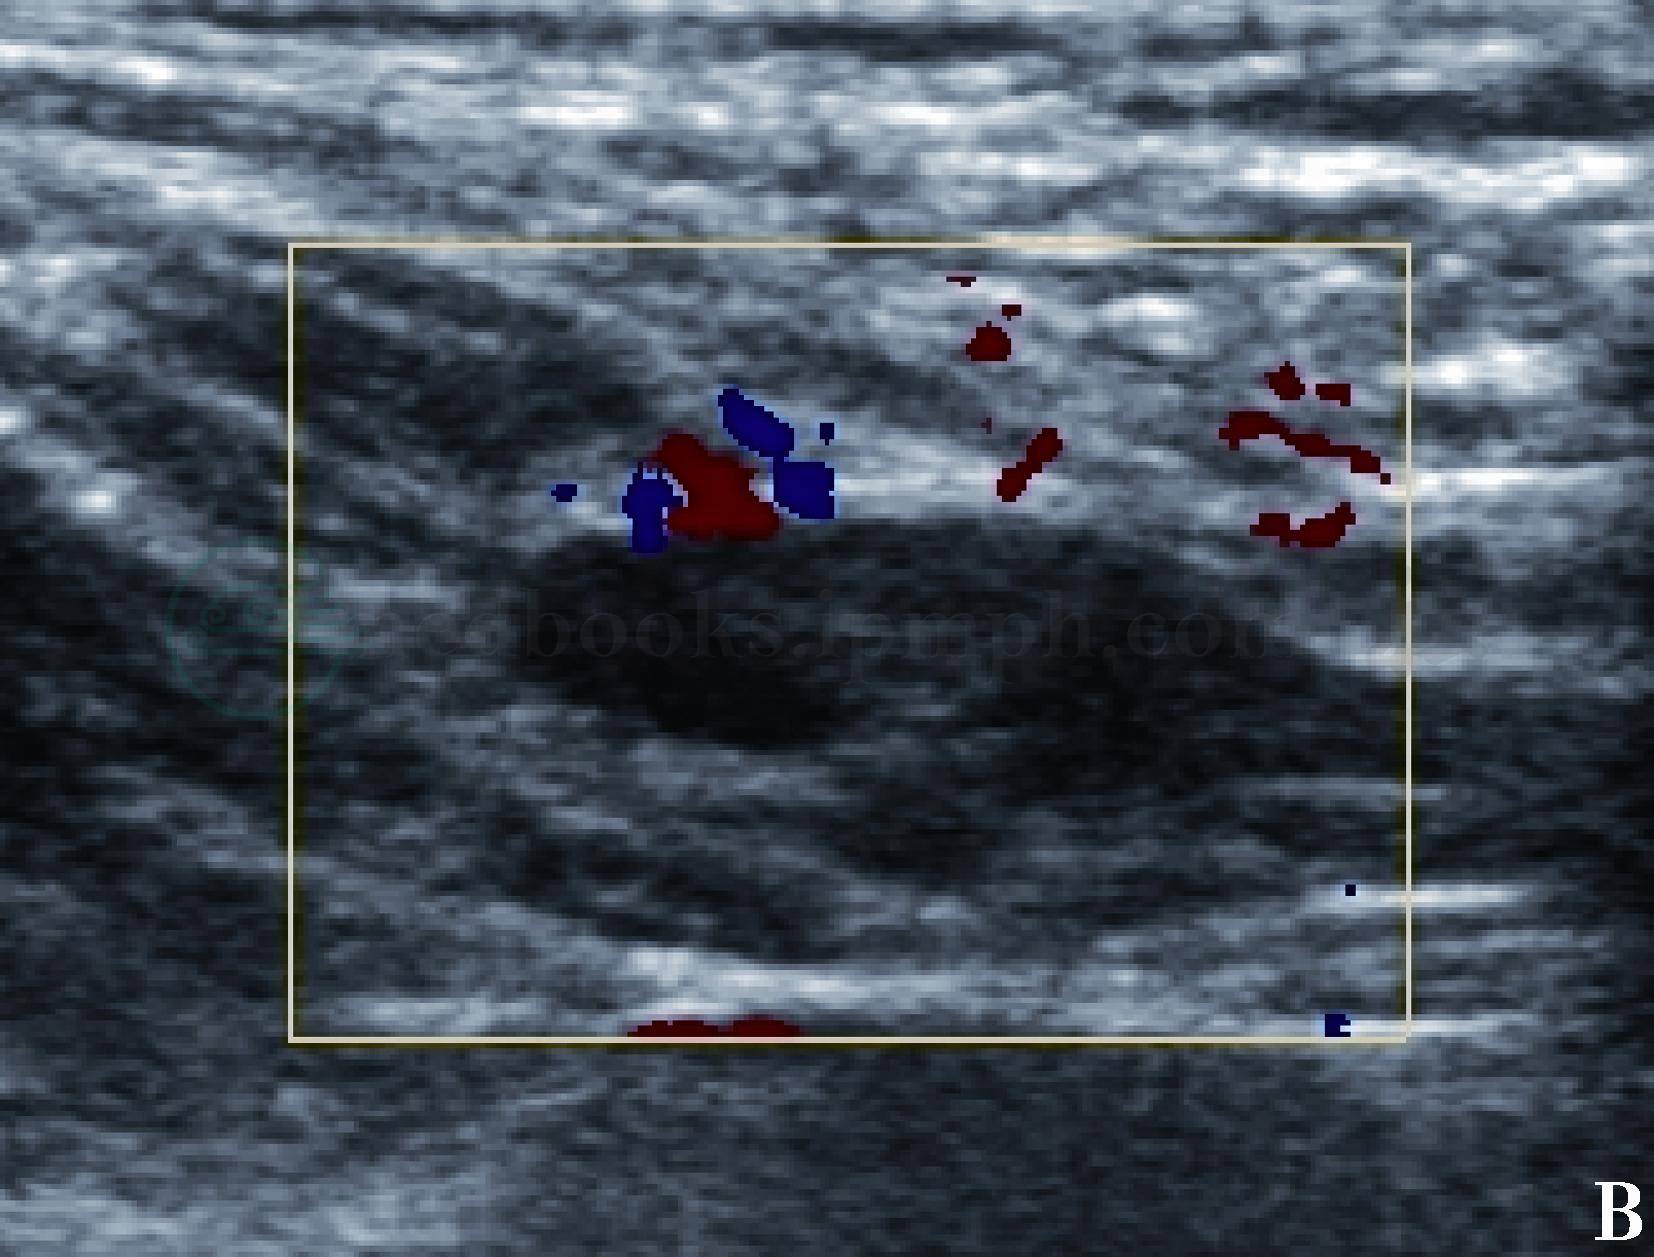

图2 正常锁骨上淋巴结声像图

彩色多普勒超声显示淋巴结内未见明确血流